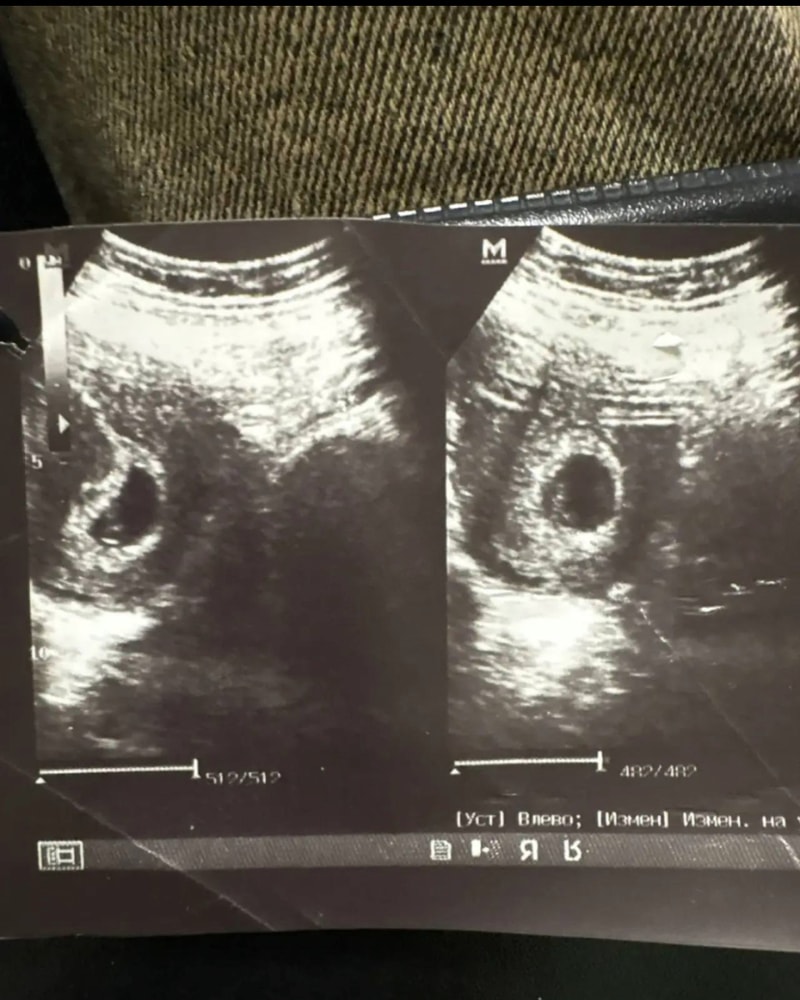

Это не её узи. Какое нахрен плодное яйцо, когда хгч 11 😅😅 девушка фантазерка. Пускай пришлёт узи где есть её фамилия, протокол с узи. Или просто на прямую скажите ей, что при хгч 11 такого узи быть не может.

При хгч 11 ещё даже задержки месячных нет, такого снимка на узи не будет при таком хгч, рано. Хгч и узи не соответствуют друг другу. Возможно это её старое хгч? Давно беременность наступила до приезда вашего сына и до их па , раз такое узи, значит давно беремена она. Жалко парня, змею пригрел.

У нее Хгч сомнительный, до 25 единиц нужно пересдавать для динамики. А учитывая разницу между 7 и 11 декабря роста вообще нет, это бхб. Снимок узи не ее, дурят вас обоих

Не от вашего сына видимо девушка была беременна или до сих пор беременна по всей видимости. Сначало наврала , возможно ради льгот,раз он на СВО. Потом возможно передумала. ХГЧ для такого срока ничтожный. А фото непонятно откуда эти взяла . При таком ХГЧ ничего бы не увидели. Если эта беременность даже и сорвалась,то эта банальная биохимическая . Таблетки для аборта в таком случае не нужны.

Ну, узи то с приличным сроком, там и эмбрион видно. Если ее, то беременность не от сына. Если не ее, соответственно врет. Ну и вы сами понимаете, что до хгч 1000 пя не видно, его и при 1000 не на каждом аппарате увидят. Не то что наличие эмбриона. Разводила девушка!

Тут в принципе какая-то лабуда 🤷🏻♀️ на ХГЧ 11 ничего не видно в принципе, на фото приличное плодное яйцо.

Как по мне всю ситуацию можно решить просто предложив сыну в джпити чат ввести видно ли эмбрион, плодное яйцо когда хгч 11. И пусть самостоятельно делает выводы или ведет разговор с ней. На узи у беременной женщины хгч явно больше 2000

Обычно на снимках печатают еще и дату месячных или срок от месячных . И замеры плодного яйца и желточного мешочка, потому что это в узи самое важное на таком сроке. На более поздем уже пишут ктр эмбриона и всегда есть заключение. Бумажное, напечатаное. Всегда! Будь то платно, или бесплатно не важно. Всегда есть заключение